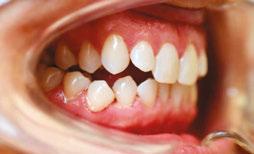

Patient J, a 39-year-old female, (Figures 1, 2, 3, 4, 5, 6) came to the office with concerns about difficulties chewing food and experiencing dry mouth upon waking up in the morning. Additionally, her partner was disturbed by her snoring. Upon examination, several issues came to light:

1. An open bite in the anterior region and a posterior crossbite

2. Breathing through the nose 10% of the time.

3. Lips and cheek muscles actively helping with swallowing food and drinks

4. Lips open 100% of the time

5. Tongue cannot maintain position on a spot, moves between teeth upon swallowing

6. Tongue thrust

7. Weak control over soft palate

Muscle tension around the temporomandibular joint (TMJ) was also evident5 as well as mandibular bilateral lingual torus as response to constant occlusal pressure applied during bruxism.

Figure 1: Swallowing with tongue trust

Figure 2: Anterior view before treatment

Figures 3 and 4: 3. Right side before treatment. 4. Left side before treatment

Figures 5 and 6: 5. Upper arch before treatment. 6. Lower arch before treatment